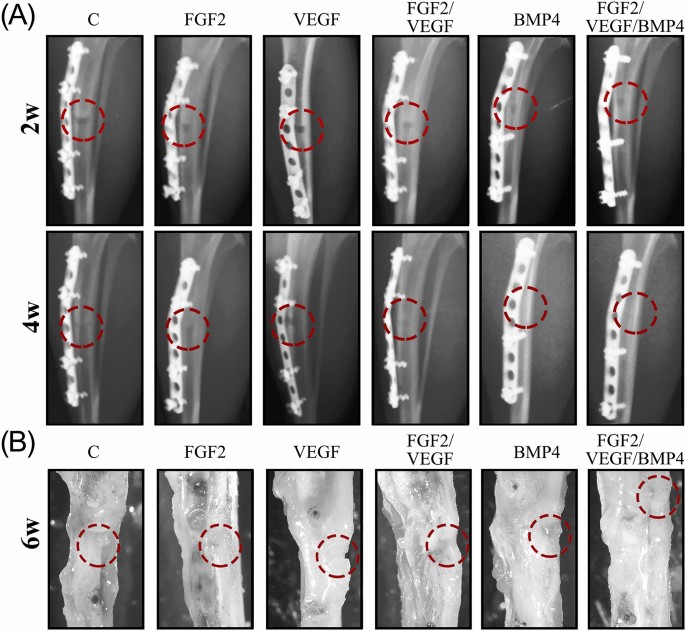

After validating titanium coatings biocompatibility in vitro, we next pursued testing of implants’ healing capacity in vivo in a rat animal model of tibia injury (see Supplementary Fig. S2 online). X-ray images at 2 weeks after surgery showed the presence of the bone defect in all investigated groups with no prominent differences among them (Fig. 2A). At 4 weeks, the bone defect persisted in the animals with implants covered with FGF2 and VEGF as revealed by the radiographs. The control and the FGF2/ VEGF groups presented a less visible defect. Oppositely, both BMP4 and FGF2/ VEGF/ BMP4 groups unveiled a defect zone filled with hard callus suggesting that the new bone presented increased mineralization (Figs. 2A, 4W). Stereomicroscope examination of the ex vivo tibiae showed the presence of the bone defect in all groups. However, it was difficult to differentiate between the edge of newly formed bone and mature bone for the FGF2/ VEGF/ BMP4 group (Fig. 2B, last panel) while the exception animal from VEGF group had a defect not completely filled with newly formed tissue at 6 weeks after operation (Fig. 2B, 3rd panel). These results suggest an essential role for BMP4 in enhancing the bone defect repair in our rat model.

Evolution of bone repair during the 6 weeks experimental period. (A) Representative radiographs of defect site of control C, FGF2, VEGF, FGF/VEGF, BMP4 and FGF/VEGF/ BMP4 groups, at 2 (2w) and 4 (4w) weeks after surgery. There were no differences among the groups regarding the healing of bone defect at 2 weeks. X-ray images at 4 weeks showed a less visible defect for BMP4 and FGF/VEGF/ BMP4 groups suggesting an accelerated repair process compared to the other groups. (B) At 6 weeks (6w) after implantation, the tibiae were evaluated using the stereomicroscope. The images (× 0.65 magnification) indicated a very good healing with hard to distinguish edges between the newly formed and mature bone only in the FGF2/ VEGF/ BMP4 group. The red circles indicate the bone defect areas.